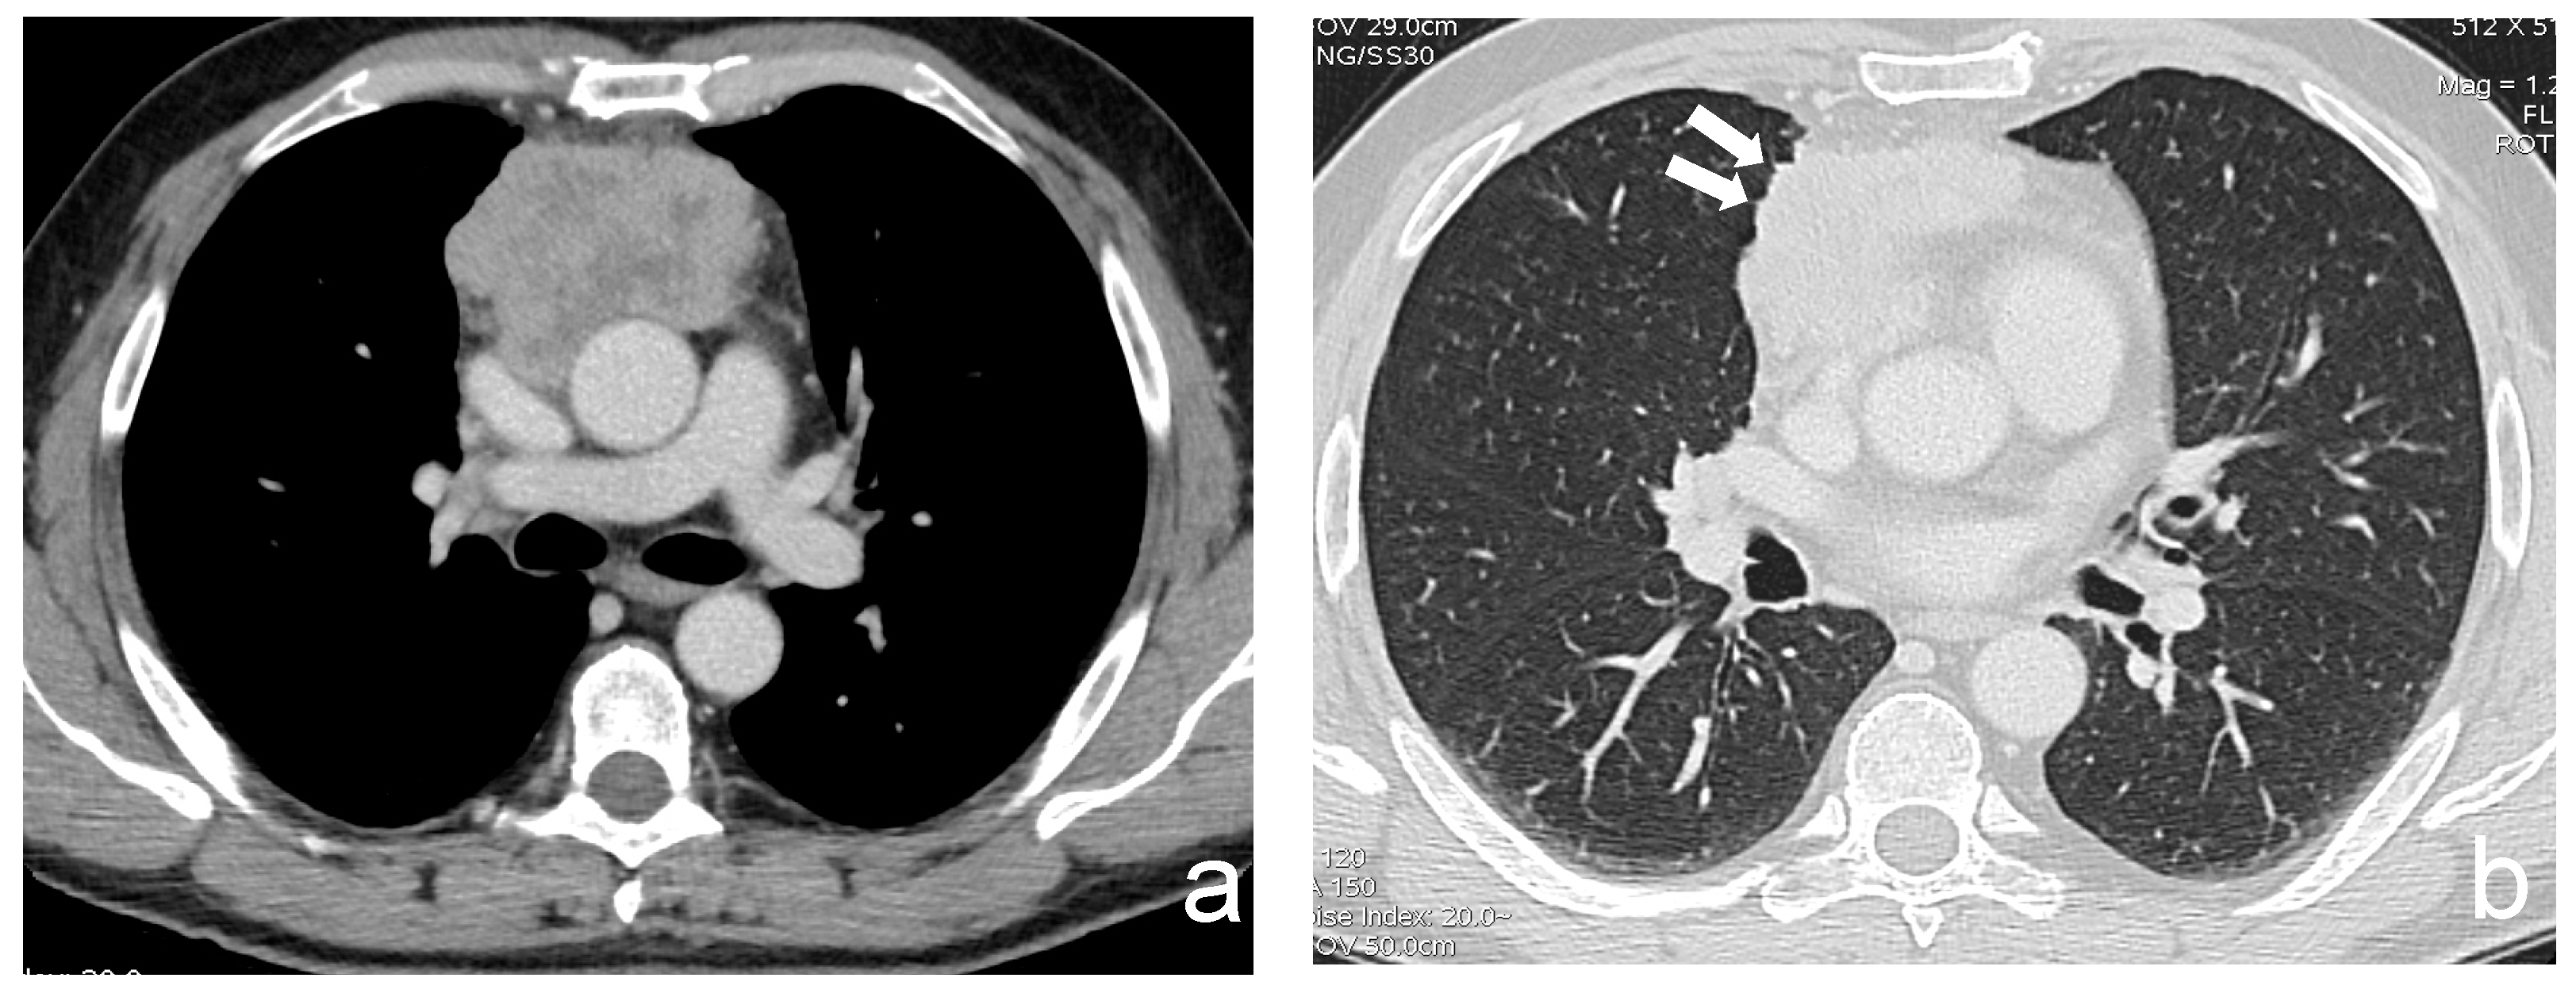

Figure 2.

(a,b) A 63-year-old man with a poor differentiated squamous thymic carcinoma invading the pericardium and the lung (stage IIIa). Margins of the lesion are multilobulated and indented at the interface with the lung; the latter CT finding is better demonstrated using a lung window (arrows).